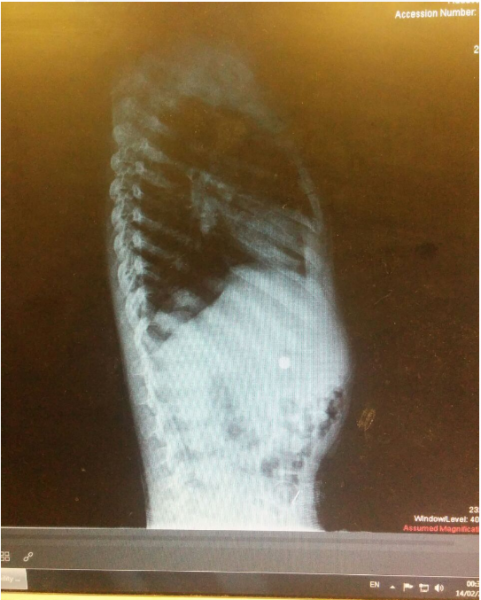

כאן לא תמו המקרים הדחופים במשמרת. כמעט במקביל הגיע ילד בן ארבע למיון, אשר בלע סוללת כפתור. המידות הקטנות של הסוללה, בסיוע החלקלקות של העצם הזר הזה, שיחקו לטובת הילד והסוללה התקדמה לכיוון היציאה הטבעית מקיבתו של הילד, זאת תחת מעקב הצוות שחשש מהרעלה מסוכנת אשר יכולה להיגרם כתוצאה מבליעתה.

סוללה בקיבתו של בן ה-4 // צילום: דוברות הדסה